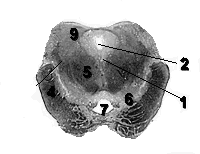

Скопление серого вещества в глубине мозжечка образует его ядра (nuclei cerebelli). Различают следующие:

Зубчатое ядро (nucleus dentatus) залегает в медиально-нижних участках белого вещества

Пробковидное ядро (nucleus embolifirmis) располагается медиально и параллельно зубчатому ядру.

Шаровидное ядро (nucleus globosus) залегает несколько медиальнее пробковидного.

Ядро шатра (nucleus fastigii) располагается в белом веществе червя, по обеим сторонам его серединной плоскости, под долькой язычка (lingula) и центральной долькой (lobulus centralis), в крыше четвертого желудочка.

Рис. 2 Ядра Мозжечка.